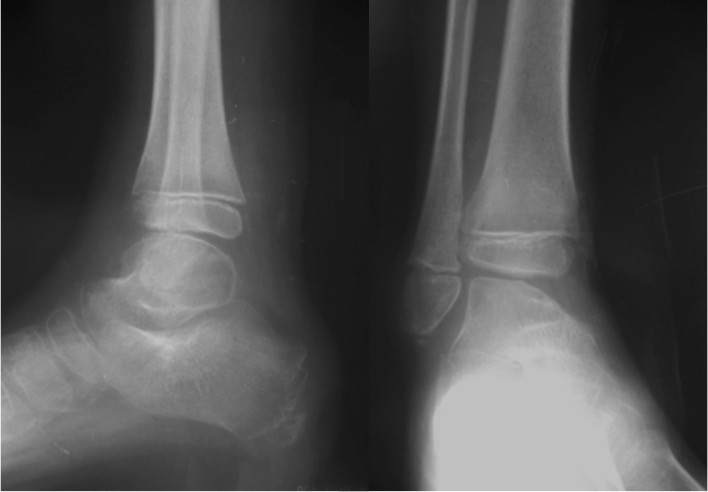

IntroducciónLas fracturas Salter-Harris VI (SHVI) son lesiones que se caracterizan por presentar ablación del anillo pericondral. Son infrecuentes en niños pero potencialmente devastadoras. El objetivo de este estudio fue evaluar el mecanismo de producción, el tratamiento y los resultados funcionales de estas lesiones localizadas en el pie y el tobillo.Material y métodosSe analizaron retrospectivamente todos los pacientes con lesiones SHVI de tobillo y pie tratadas entre Enero de 2010 y Enero de 2013. Se documentaron datos demográficos, clasificación, mecanismo de lesión, tipo de lesiones asociadas y número de cirugías que requirieron. Los pacientes fueron evaluados funcionalmente con el score de AOFAS y radiográficamente para determinar la viabilidad de la fisis, acortamiento del miembro o deformidad angular.ResultadosSe analizaron 5 fracturas en 4 pacientes (3 masculinos y 1 femenino). La edad promedio al momento de la lesión fue de 7.5 años (rango, 6 a 10 años). El seguimiento promedio fue de 26.2 meses (rango, 12 - 37 meses). De acuerdo a la subclasificación de Peterson 3 pertenecían al grupo A, 1 al B y 1 al C. 3 lesiones se produjeron como consecuencia de accidentes de moto y 2 por auto versus peatón. Todos los casos se acompañaron de pérdida de sustancia, el 75% presentaba lesiones en más de un hueso y el 50% lesiones tendinosas asociadas. Cada paciente requirió un promedio de 3.2 cirugías (rango, 2 a 5). El score AOFAS promedio fue de 79.8 puntos (rango, 62 – 100 puntos). Radiográficamente, solo el 40% de las fisis afectadas permanecían viables al último control.ConclusiónLas fracturas SHVI se acompañan de una gran variedad de lesiones asociadas, requieren múltiples cirugías y suelen producir un cierre precoz de la fisis y algún grado de discapacidad. Se requieren medidas de prevención para evitar la exposición de los niños a este tipo de lesiones. El tratamiento temprano es fundamental para prevenir el desarrollo de deformidades.Descargas